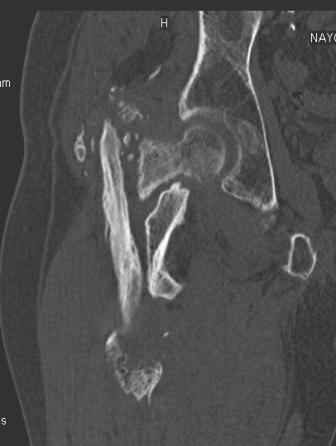

Уважаемый Глеб! Укорочение наверное побольше, да и наружно-ротационная установка скорее всего присутствует. Суставная щель прекрасная, головка живее всех живых. Ратую за подвертельную с латерализацией: исключает нарушение механической оси («исключает вальгус в коленe»), максимально удлиняет без натяжения m.iliacus. Для иллюстрации остеотомия-переделка (слава богу не автопеределка) у мужчины 65 лет.

Филипчук.

PS. Извините за качество последнего снимка, рентгенограмма выполнена по м. жительства, там где был проведен синтез. Последний снимок выполнен через 2 мес. п\о, больной без разрешения начал наступать, слава богу все обошлось.